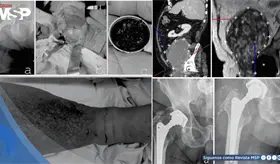

Las prótesis antiguas de metal con metal pueden liberar partículas microscópicas que generan inflamación severa, masas que imitan tumores malignos y, además, crean un ambiente propenso a infecciones profundas difíciles de tratar.